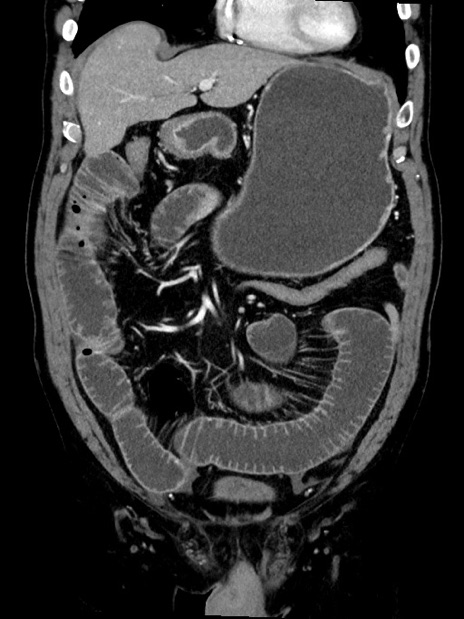

症例35(冠状断像)

【症例】70歳代 男性

【主訴】腹部膨満、嘔吐

【現病歴】昨日より腹部膨満感出現。本日増悪し、仙痛出現。嘔吐あり、受診。

【既往歴】糖尿病、胆摘後

【身体所見】BP 149/80mmHg、HR 74/min、BT 35.9℃、腹部:膨満、軟、圧痛なし。腸雑音減弱あり。上腹部正中切開瘢痕あり。

【データ】WBC 13500、CRP 1.72